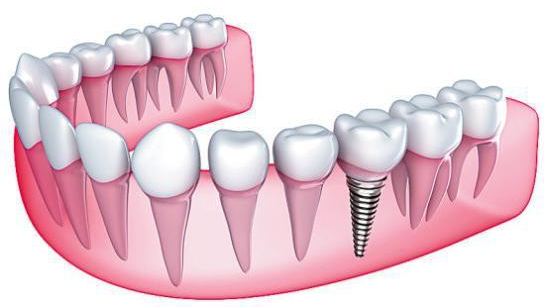

缺了牙怎么办呢?别急,我们还有种植牙。相信大家在很多地方都了解过种植牙这个词,种植牙凭借其逼真的自然牙外形和咀嚼使用功能一举成为缺牙者的优选修复方式。

安装愈合基台(可以把基台简单粗糙理解为螺帽)。使种植体穿出牙龈,等待软组织成形。

05、换上永久基台

在差不多2--3周后,软组织成形后。医生会用永久基台换下愈合基台。

06、佩戴牙冠

将制作好的牙冠套在永久基台上,自此,种植牙就大功告成。